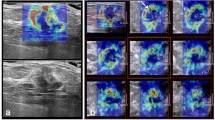

Shear wave elastography (SWE) is an emerging technique which can obtain quantitative elasticity values in breast disease. We therefore evaluated the diagnostic performance of SWE for the differentiation of breast masses compared with conventional ultrasound (US). Conventional US and SWE were performed by three experienced radiologists for 158 consecutive women who had been scheduled for US-guided core biopsy or surgical excision in 182 breast masses (89 malignancies and 93 benign; mean size, 1.76 cm). For each lesion, quantitative elasticity was measured in terms of the Young’s modulus (in kilopascals, kPa) with SWE, and BI-RADS final categories were assessed with conventional US. The mean elasticity values were significantly higher in malignant masses (153.3 kPa ± 58.1) than in benign masses (46.1 kPa ± 42.9), (P < 0.0001). The average mean elasticity values of invasive ductal (157.5 ± 57.07) or invasive lobular (169.5 ± 61.06) carcinomas were higher than those of ductal carcinoma in situ (117.8 kPa ± 54.72). The average mean value was 49.58 ± 43.51 for fibroadenoma, 35.3 ± 31.2 for fibrocystic changes, 69.5 ± 63.2 for intraductal papilloma, and 149.5 ± 132.4 for adenosis or stromal fibrosis. The optimal cut-off value, yielding the maximal sum of sensitivity and specificity, was 80.17 kPa, and the sensitivity and specificity of SWE were 88.8% (79 of 89) and 84.9% (79 of 93). The area under the ROC curve (Az value) was 0.898 for conventional US, 0.932 for SWE, and 0.982 for combined data. In conclusion, there were significant differences in the elasticity values of benign and malignant masses as well as invasive and intraductal cancers with SWE. Our results suggest that SWE has the potential to aid in the differentiation of benign and malignant breast lesions.